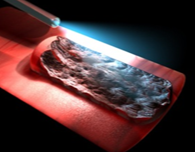

The Hemera Thulium Laser offers high-speed performance regardless of the size of the gland, vasculature and morphology. the surgeon can, then, choose whether to use vaporization, vaporesection or technical enucleation

Hemera Thulium Laser remains effective even after many passages. Thulium laser is superior due to the possibility to emit both in continuous and pulsed mode. A continuous emission with the ability to vaporesect with lower costs due to the possibility of using multiple – time reusable fibers instead of disposable ones.

Hemera Thulium Laser emits energy more efficiently and more predictably on targeted tissue, independently from their blood percentage. The optical penetration depth is uniform. The technique of laser coagulation with Hemera Thulium Laser can be performed by directing the laser beam directly on the blood flow. The side effects of postoperative bleeding and dysuria are way inferior to those of each other laser method.